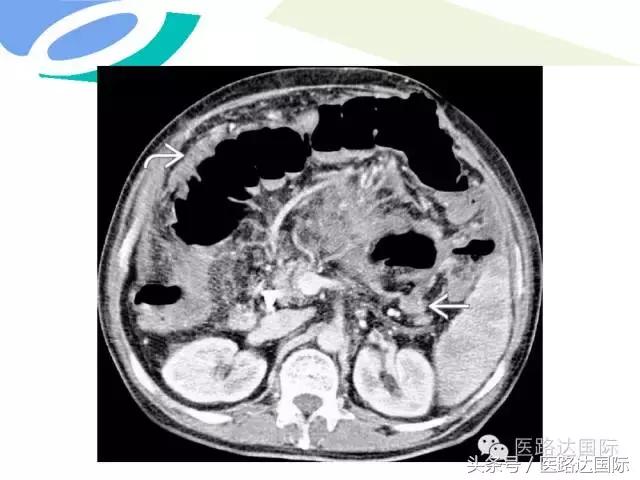

首都医科大学附属北京妇产医院梁宇霆教授从流行病学、临床特点、实验室检查、病理改变、影像学特点及治疗与预后六个方面向我们详细地介绍了女性生殖系统结核;并且着重介绍了子宫输卵管造影(HSG)的作用。在最后,梁教授还向大家介绍了如何鉴别诊断女性生殖系统结核、盆腔炎性病变和卵巢癌。